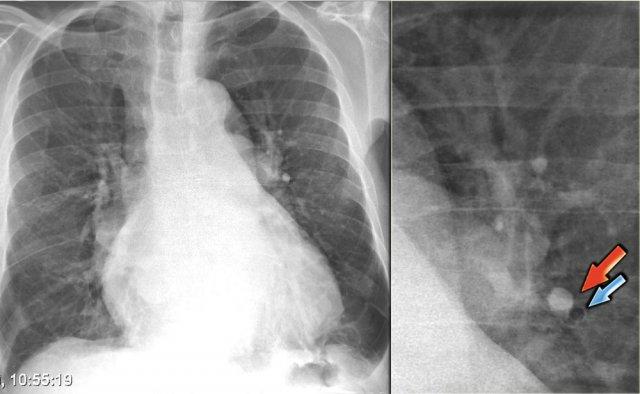

Hình minh họa bên trái thể hiện một số đặc điểm có thể quan sát được trên phim X-quang ngực của bệnh nhân suy tim sung huyết.

Hình ảnh các mạch máu thùy trên của bệnh nhân trong tình trạng bình thường (trái) và trong giai đoạn suy tim sung huyết (phải). Lưu ý độ rộng tăng lên của cuống mạch máu (mũi tên đỏ).

Bên trái là hình ảnh bệnh nhân có tim to và tái phân phối.

Các mạch máu thùy trên có đường kính > 3 mm (bình thường 1-2 mm).

Lưu ý tỷ lệ động mạch/phế quản tăng ở mức rốn phổi (mũi tên).

Bên trái là hình ảnh bệnh nhân suy tim sung huyết.

Có sự tăng khẩu kính của các mạch máu phổi và chúng mất nét bờ do bị bao quanh bởi phù nề.

X-quang ngực bình thường trước đó (trái) và suy tim sung huyết giai đoạn II với mờ quanh rốn phổi (phải)

Bên trái là hình ảnh một bệnh nhân khác bị suy tim sung huyết.

Tư thế chụp nghiêng thể hiện rõ sự tăng đường kính của các mạch máu phổi và bờ mờ nhạt của chúng.

Lưu ý cũng có các đường vách và mô kẽ nổi bật.

Ngoài ra, khe liên thùy lớn dày lên rõ rệt.

Bên trái là hình ảnh bệnh nhân nhập viện với khó thở nặng do suy tim cấp.

Các dấu hiệu sau đây gợi ý suy tim: phù phế nang với đông đặc quanh rốn phổi và dấu hiệu phế quản hơi (mũi tên vàng); tràn dịch màng phổi (mũi tên xanh lam); tĩnh mạch đơn nổi bật và độ rộng cuống mạch máu tăng (mũi tên đỏ) và bóng tim to (đầu mũi tên).

Sau điều trị, chúng ta vẫn có thể thấy bóng tim to, tràn dịch màng phổi và tái phân phối lưu lượng máu phổi, nhưng phù nề đã được giải quyết.